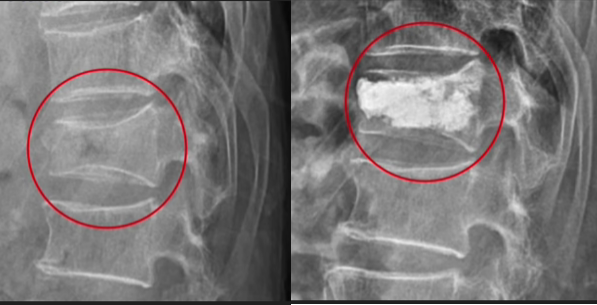

7) 척추압박골절 : 골다공증이 없이 발생하는 경우는 높은 데서 떨어져 발생하는 낙상일 때 주로 발생합니다.

이런 경우는 노동력이 있는 젊은 연령층에서 주로 발생합니다.

반면 고령층이 증가하고 있는 요즘에는 가벼운 엉덩방아를 찧거나

미끄러져 주저앉기만 해도 척추체가 찌그러지는 손상을 입을 수 있습니다.

이런 분 들은 대부분이 골다공증으로 인한 골절인 경우가 많습니다.

신경관을 심하게 압박하는 경우 응급수술을 필요로 하기도 하는 데 신경관을 침범하지 않는 경우는

보통 골시멘트 주입술을 통해 찌그러진 것을 복원해 주는 간단한 시술을 통해 회복될 수 있습니다.